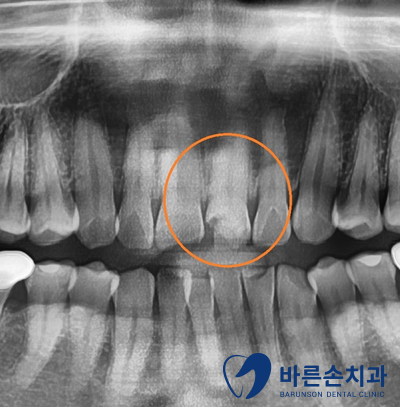

정확한 손상 정도를 확인 하기 위해 엑스레이 촬영을 합니다

엑스레이 확인 결과 육안상으로 보는 것 보다

파절정도와 범위가 크고 이로인해 치아의 신경이 노출된 것을 알 수 있었습니다